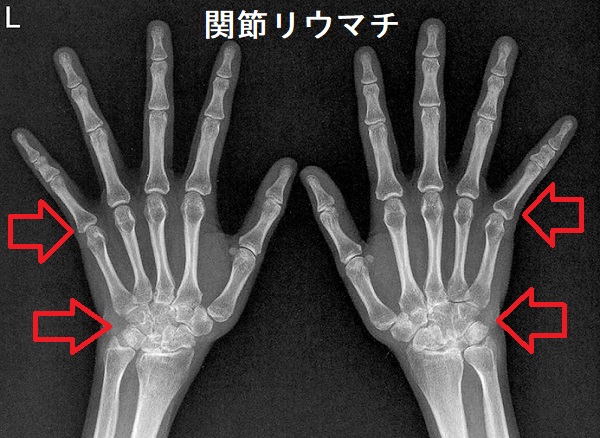

関節リウマチ(RA)は、免疫系が自分自身の組織を攻撃する自己免疫が原因の関節炎(滑膜炎)です。関節リウマチ(RA)では、

- 左右対称性に手足の関節が腫れ、関節を動かさなくても激しい痛みが生じる(他の関節の病気と異なる点)

- 関節の軟骨や骨が破壊され、関節変形に至る

骨関節X線(レントゲン)検査